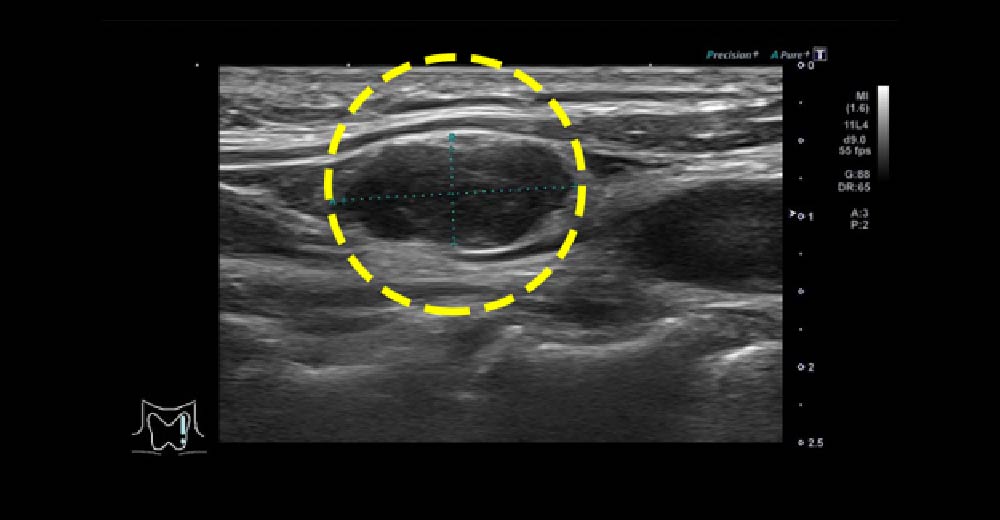

甲状腺乳頭がん

甲状腺右葉に境界不整、辺縁不整、内部不均一で一部石灰化を伴い、長径30mm程度の内部血流を伴う腫瘤を認めます。甲状腺全摘に至りました。

甲状腺乳頭がん 甲状腺乳頭がん